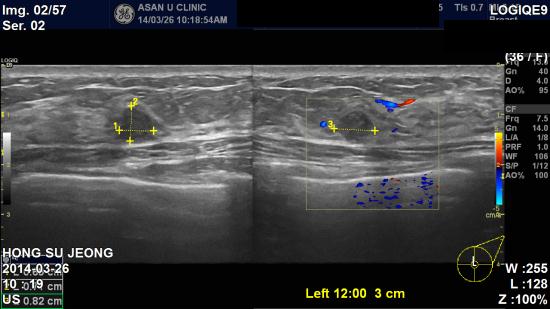

좌측유두에서 피가나와 내원하신 36세 여성분이십니다.

본원 초음파검사상 의심되는

좌측

2곳과

우측

2곳을

조직검사시행하였고

,

좌측은 비정형유관증식증,

우측은 상피내암으로

진단되었습니다

.

이처럼 피가 나왔던 좌측 유방,

즉 증상이 있는

부위가 아닌 반대쪽 유방에서 암이 발견되는 경우도 있습니다